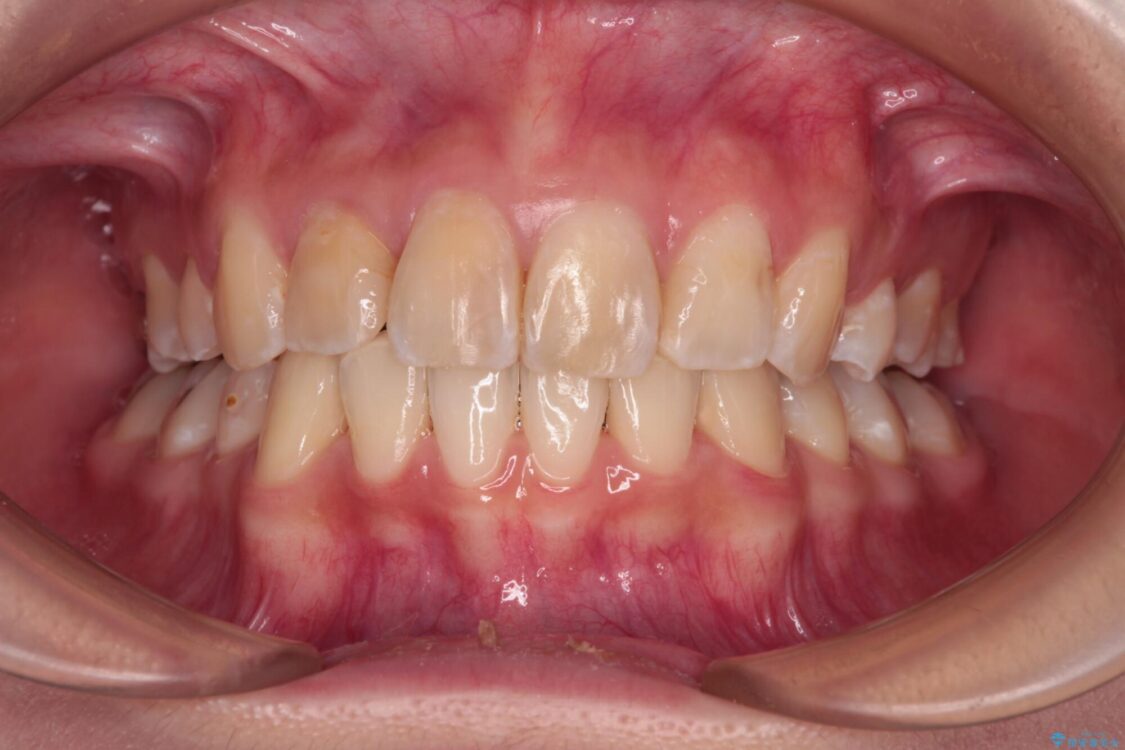

内側に倒れ込んだ歯や下の前歯が隠れてしまうほどの咬み合わせを改善したいとのことで来院された患者様です。

治療前

• デコボコと深い咬み合わせ ワイヤー装置での抜歯矯正 治療前画像